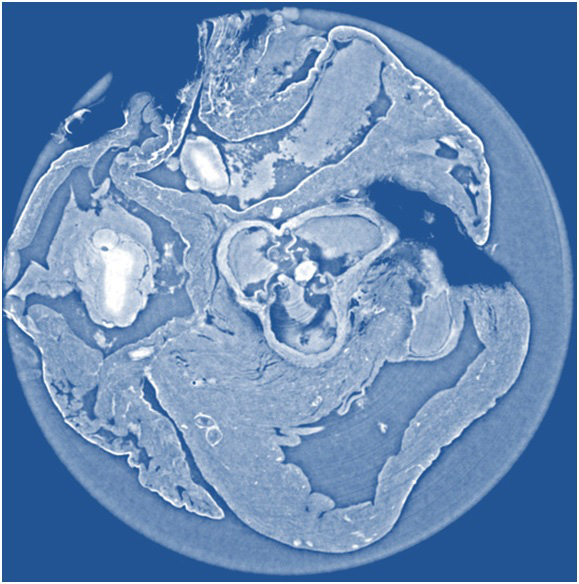

Immagine ottenuta in modo non invasivo della sezione del tessuto cardiaco di un topo realizzata con tomografia X a contrasto di fase “propagation-based”, metodo che fornisce immagini più nitide, e con una risoluzione superiore, rispetto agli altri due considerati nello studio. Crediti: Irene Zanette/Technische Universität München

È infatti con raggi X di alta qualità prodotti dalla radiazione di sincrotrone che un team di scienziati, sfruttando l’acceleratore della European Synchrotron Radiation Facility (ESRF), ha messo a confronto tre diverse tecniche di tomografia a contrasto di fase: interferometrica con reticolo, propagation-based con ricostruzione di fase single-distance e olotomografia. I risultati sono pubblicati sull’ultimo numero del Journal of Applied Physics, e dicono che i tre metodi, per quanto riguarda il loro impiego in ambito diagnostico, sono complementari.